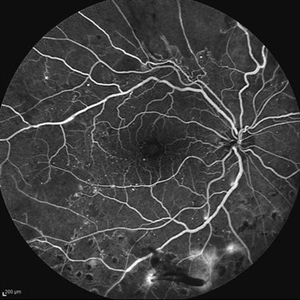

Behcet's Disease Behcet's DiseaseMar 13 2013 by Hamid Ahmadieh, MD Late phase FA of the right eye of a 23-year-old man with retinal vasculitis and branch retinal vein occlusion (BRVO) due to Behcet's disease . Photographer: Solmaz Shahmohammad, Negah Eye Center, Tehran Imaging device: Heidelberg Spectralis Condition/keywords: branch retinal vein occlusion (BRVO), retinal vasculitis

Behcet's Disease Behcet's DiseaseMar 13 2013 by Hamid Ahmadieh, MD Wide field FA of the right eye of a 23-year-old man with retinal vasculitis and branch retinal vein occlusion (BRVO) due to Behcet's disease . Photographer: Solmaz Shahmohammad, Negah Eye Center, Tehran Imaging device: Heidelberg Spectralis Condition/keywords: branch retinal vein occlusion (BRVO), retinal vasculitis